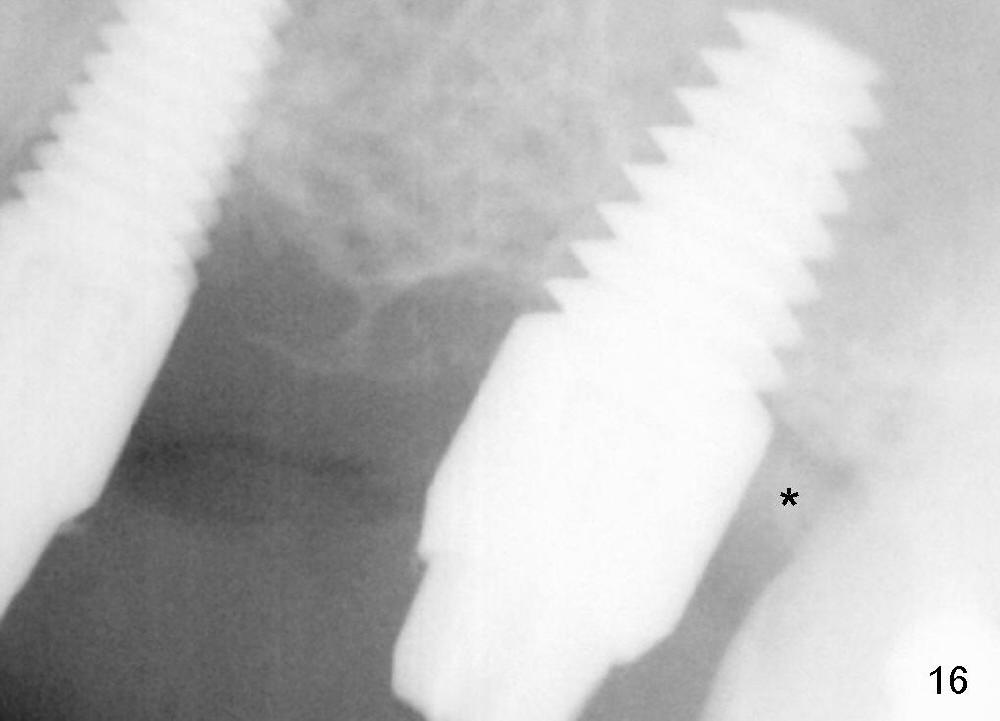

Two PAs are taken 5 months postop (Fig.15,16). Patterns of bone graft (*) between these PAs are different, which suggests presence of the graft buccal to the implant at the site of #14. Another piece of evidence of the graft is that the buccal socket heals (Fig.17 B) without implant thread exposure (Fig.19). These two implants are ready for definitive restoration (Fig.18-20). Fig.21 shows the final restoration 5 months post cementation.